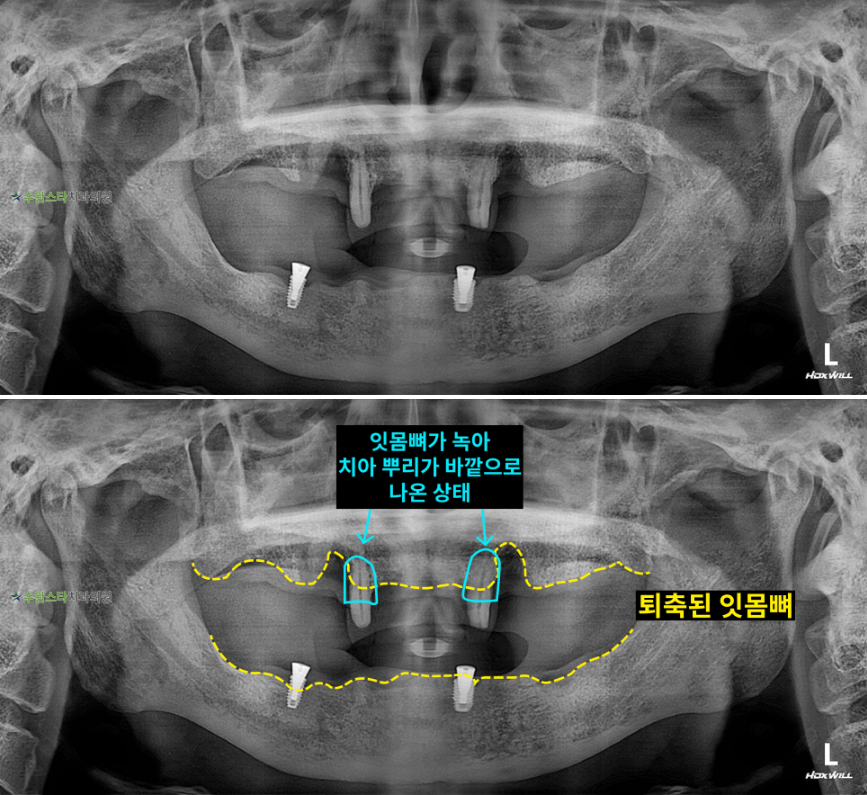

내원 시 파노라마

내원 시 파노라마, 60대 남성 (2025.11 촬영)

내원 시 파노라마 사진입니다.

위아래 잇몸뼈가 균일하지

않게 녹아내려

퇴축되어 있는 모습이기 때문에

발치 후 뼈 이식을 동반한

임플란트가 필요한데요.